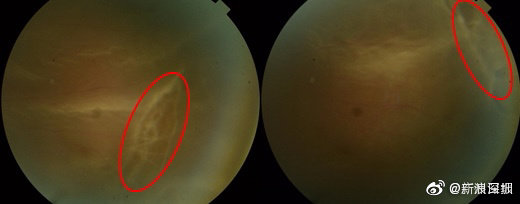

休闲区 高度近视男子踢足球后视网膜裂了 需终身避免剧烈运动 2022-01-22 20:00 0 192 0 Share 【#高度近视男子踢足球后视网膜裂了# 需终身避免剧烈运动[衰]】近日,深圳一名患有高度近视的研一学生小江(化名)眼前出现阴影,两天后和同学踢球时,奋力用头大力顶了一下球,眼前的阴影越变越大。经检查,小江左眼的视网膜上方有两大片裂孔。随后,医生为小江做了左眼视网膜脱离修复术。在小江的出院小结上,医生写下了“终身避免剧烈运动”的医嘱。 医生提醒,高度近视人群,尤其要注意避免剧烈运动或者突然性的撞击,例如,过山车,蹦极,跳水,还有外物的突然撞击。(广州日报) 相关文章泰州一女子剧烈咳嗽导致视网膜脱落 医生:高度近视者要当心网友自述近视12000度,高度近视到底有多可怕?44岁“摘镜”是一种什么样的体验?TICL助高度近视的她重获高清“视”界上汽名爵、荣威汽车推出零燃保障 + 三电终身质保:不限里程、新老车主可享比亚迪方程豹豹 5 第二次 OTA 将至:仪表显示海拔信息、语音可调云辇悬架高度赠送电池终身质保 / 付费轮辋限时 5 折,小鹏汽车 618 购车优惠公布可选翻转屏、强调高度可维修性:华硕五款笔记本亮相英国教育展今起无人机需实名登记“身份证”,适飞高度不超 120 米 标签:剧烈 · 终身 · 视网膜 · 近视 · 高度 0